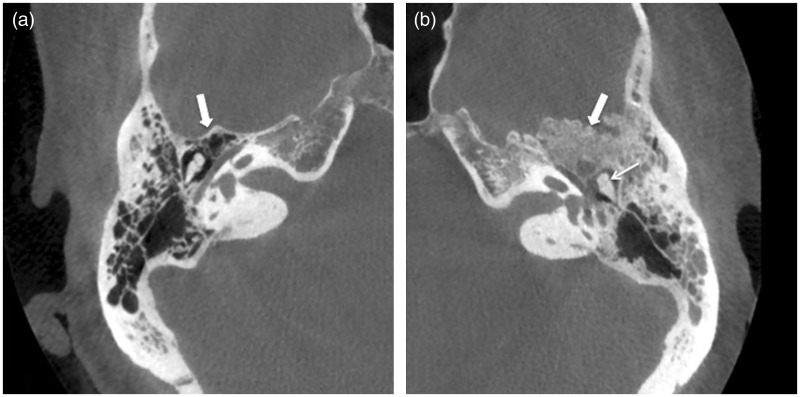

我们报告一例颞骨脑膜瘤延伸到中耳腔,临床表现为浆液性中耳炎的影像特征。颞骨脑膜瘤延伸至乳突或中耳腔,是非常罕见的。如果原因不明或治疗抵抗浆液性中耳炎和鼻咽肿瘤被排除,应进行颞骨计算机断层扫描(CT)。如果CT表现提示颞骨脑膜瘤,则磁共振成像(MRI)加钆检查将确认诊断并显示病变的确切范围。

We report the imaging features of a case of a temporal bone meningioma extending into the middle ear cavity and clinically presenting as a serous otitis media. Temporal bone meningioma extending in the mastoid or the middle ear cavity, however, is very rare. In case of unexplained or therapy-resistant serous otitis media and a nasopharyngeal tumor being ruled out, a temporal bone computed tomography (CT) should be performed. If CT findings are suggestive of a temporal bone meningioma, a magnetic resonance imaging (MRI) examination with gadolinium will confirm diagnosis and show the exact extension of the lesion.